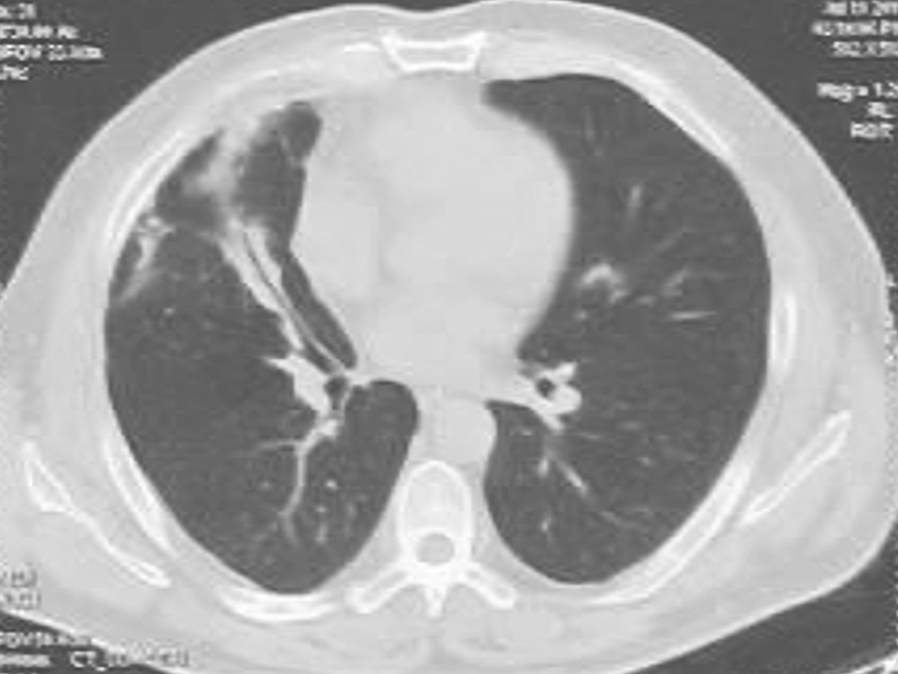

自2月18日起,患者体温高峰<37.3℃,采取抗感染降阶梯治疗,头孢哌酮联合舒巴坦(3g,每12小时1次)、克林霉素(0.6g,每12小时1次)、左氧氟沙星(0.5g,每天1次)5天,然后氨苄西林联合舒巴坦(3g,每8小时1次)、多西环素(0.1g,每天2次)7天。患者体温持续正常,咳嗽、咳痰明显减轻,于3月11日出院。出院后,口服抗生素多西环素(0.1g,每天2次)、阿莫西林克拉维酸(0.625g,每天2次)4个月。期间,患者于3月22日在当地医院行支气管镜检查,未见异常;4月22日复查胸部CT示右肺空洞消失,遗留粗大索条、局限性胸膜病变(图4);7月28日复查胸部CT示右中叶索条影(图5)。

图4 复查胸部CT表现(2011-04-22)

图5 复查胸部CT表现(2011-07-28)